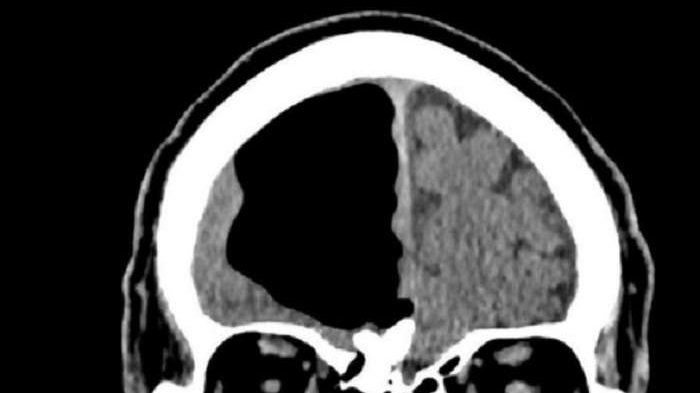

JAKARTA - Pensiunan tentara Rusia tak menyangka saat tahu bahwa ada 'lubang hitam' di otaknya. Seharusnya, tempat itu terisi oleh otak kiri. Demikian dilaporkan Dailymail.co.uk.

"Terdapat kegagalan sirkulasi darah di otak. Hal ini berbeda dari stroke ketika bagian otak rusak permanen. Bagian otak dari si pensiunan yang seharusnya jadi lokasi stroke ringan, malah tidak ada sama sekali. Justru hanya terlihat lubang hitam di gambar komputer," ujar ahli saraf Dr Marina Anikina yang menginvestigasi kasus tersebut.

Bagian otak yang hilang bisa terjadi karena kegagalan berkembangnya otak saat janin masih dalam kandungan. Ketika separuh bagian otak rusak, bagian yang lain kemudian menggantikan semua fungsinya.

Belum diketahui apa yang mengisi lubang pada tempurung otak si pria. Kasus langka serupa disebut hydranencephaly, yakni tak ditemukannya jaringan padat otak dan terisi dengan cairan.